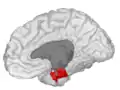

Medial surface of right hemisphere. Entorhinal cortex visible at near bottom.